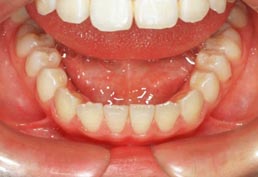

乳歯反対咬合(子どもの歯の受け口)

治療前

治療後